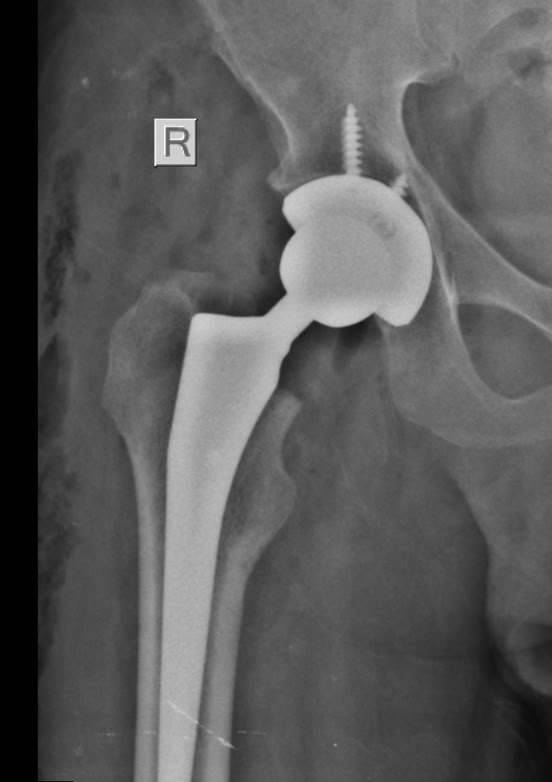

Pase de visita para preparar el parte de los quirófanos del lunes . Teníamos dos pacientes para prótesis de cadera, algunas fracturas abiertas para fijadores  y algunas cosas más que fueron  programadas. Y el lunes  después de el rezo en la capilla y la presentación de los miembros de la expedición, comenzamos el trabajo en quirófano y en consultas